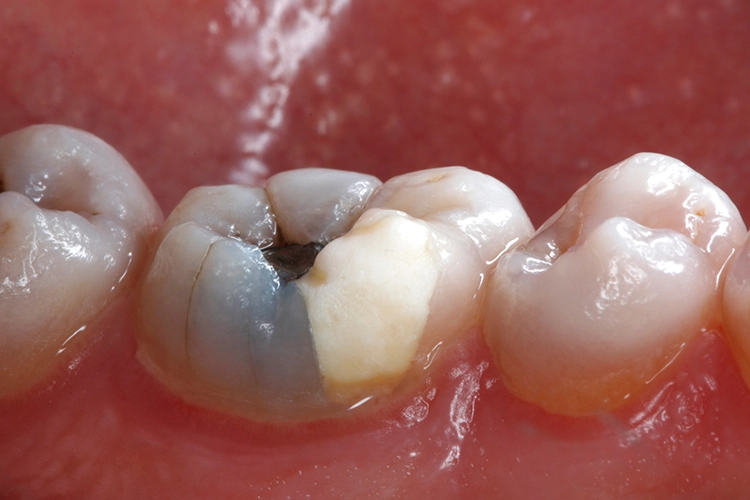

Ein 38-jähriger Patient erschien in unserer Sprechstunde mit einem frakturierten mesiolingualen Höcker neben einer okklusalen Amalgamfüllung am unteren rechten 1. Molaren (Zahn 46). Der Vorfall hatte sich bereits vor einer Woche ereignet, der Zahn war noch am selben Tag im zahnärztlichen Notdienst provisorisch mit einer Glasionomerzementfüllung versorgt worden (Abb. 1). Der Defekt erstreckte sich bis auf Höhe der marginalen Gingiva (Abb. 2).